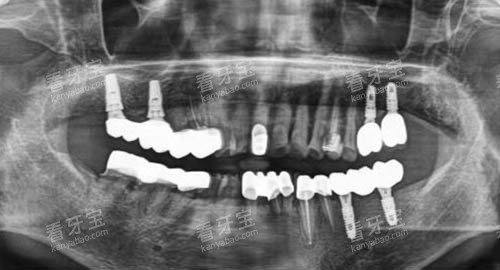

为了给患者提供更更准一些、较高的效率的治疗,贵阳龅牙兔口腔引进了一系列靠前的口腔医疗设备。

例如,智能化口腔全景机能够快速、比较准地拍摄口腔全景片,帮助医生齐全了解患者口腔的整体情况;口腔CT设备则可以提供更详细的三维影像,为种植牙等复杂手术提供精细的诊断依据。

靠前的设备不仅提高了诊断的比较准性,还缩短了治疗时间,减少了患者的痛苦。